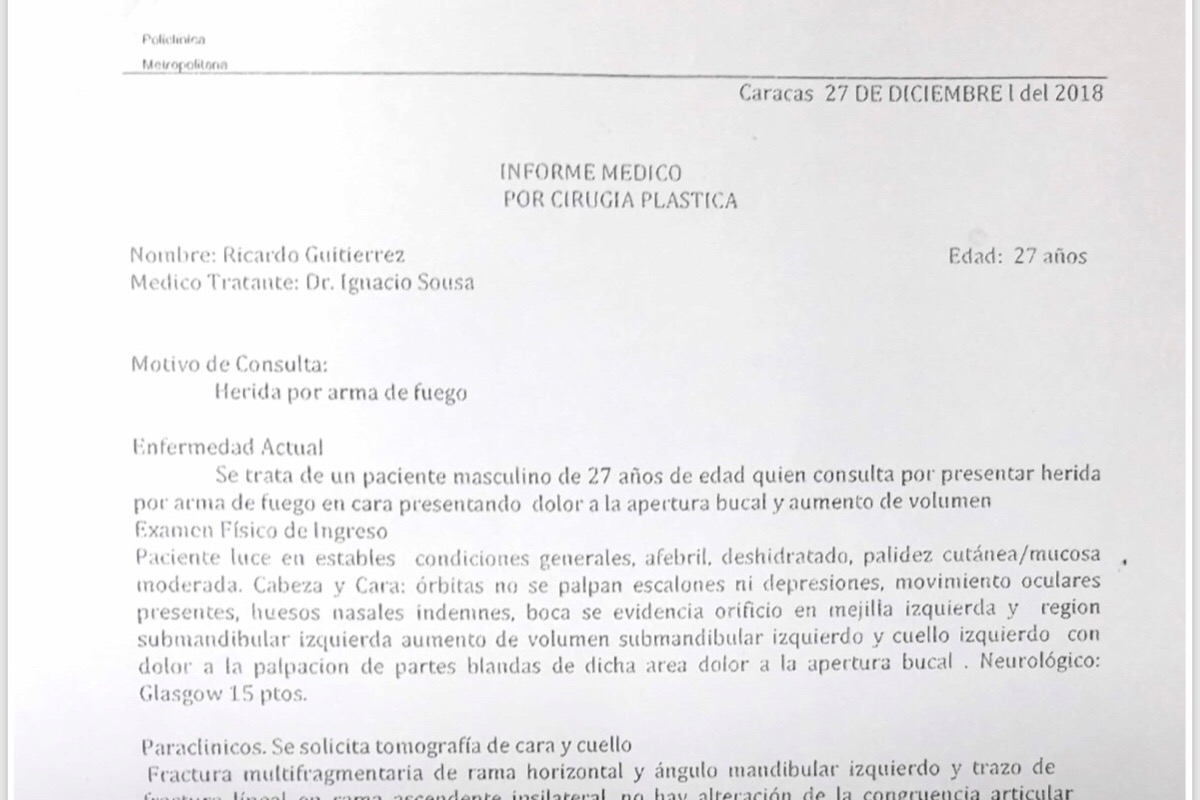

Vive en Caracas, exactamente en Residencias La California, el Marqués. Saliendo a trabajar, este 26 de diciembre. Ricardo se encontró con 2 sujetos en la planta baja de su edificio. Ellos quisieron agarrarlo y hacerlo subir a su apartamento para robarlo y robar a toda su familia. Como se opuso a dicha acción, le DISPARARON en la cara, a la altura de la mandíbula.

Adjuntas las fotos del suceso, cuentas medicas, y otras documentaciones que respaldan el suceso.

Vive en Caracas, exactamente en Residencias La California, el Marqués. Saliendo a trabajar, este 26 de diciembre. Ricardo se encontró con 2 sujetos en la planta baja de su edificio. Ellos quisieron agarrarlo y hacerlo subir a su apartamento para robarlo y robar a toda su familia. Como se opuso a dicha acción, le DISPARARON en la cara, a la altura de la mandíbula.

Adjuntas las fotos del suceso, cuentas medicas, y otras documentaciones que respaldan el suceso.